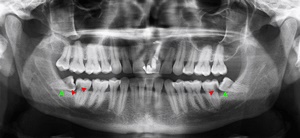

사랑니란?

우리가 사랑니라고 부르는 것은 큰 어금니 중 세 번째 위치에서 제일 마지막에 나오는 치아입니다. 사랑니가 나올 때에는 첫사랑을 하듯이 아프다고 하여 붙여진 이름이라고 하는데요. 다른 이름으로는 ‘지치’라고 합니다. 지치는 사리를 분별할 수 있는 지혜가 생긴다는 뜻입니다.

사랑니는 보통 큰 어금니와 비슷하게 생겼습니다. 사랑니의 형태나 크기는 매우 다양하다고 하는데요. 보통의 어금니 보다 깊이 나기 때문에 빼기 어렵거나 절개를 통해 힘들게 빼야 하는 경우가 많습니다. 원래 사랑니는 음식물을 갈아 내기 위한 용도라고 하는데요. 이것은 치아의 퇴화 현상이라고 생각하시는 분들도 많이 계십니다.